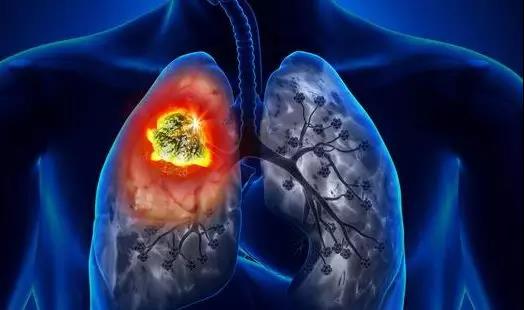

在这项研究中,研究人员发现肺癌干细胞依赖氧化磷酸化来产生细胞所需能量,维持细胞存活,并且这一过程依赖线粒体柠檬酸转运蛋白SLC25A1的活性。

研究结果表明在癌症干细胞中SLC25A1在维持线粒体柠檬酸储备和氧化还原平衡方面发挥重要作用,抑制SLC25A1的活性会导致活性氧簇的积累因此抑制癌症干细胞的自我更新能力。

研究人员进一步发现在不同的病人来源肿瘤中,肿瘤对化疗药物顺铂和EGFR抑制剂治疗的抵抗作用需要通过SLC25A1介导的线粒体活性,诱导癌细胞表现出干性表型。他们找到一类新的SLC25A1特异性抑制剂,发现与顺铂或EGFR抑制剂联合使用能够产生更好的效果,重新恢复细胞和动物模型的抗肿瘤应答反应。

这些研究结果揭示了具有药物抗性的肺癌干细胞存在代谢弱点,具有重要临床其实,该研究还发现了一类新的SLC25A1抑制剂,证明通过药物阻断SLC25A1活性,结合传统的抗肿瘤药物能够产生更好的治疗效果。